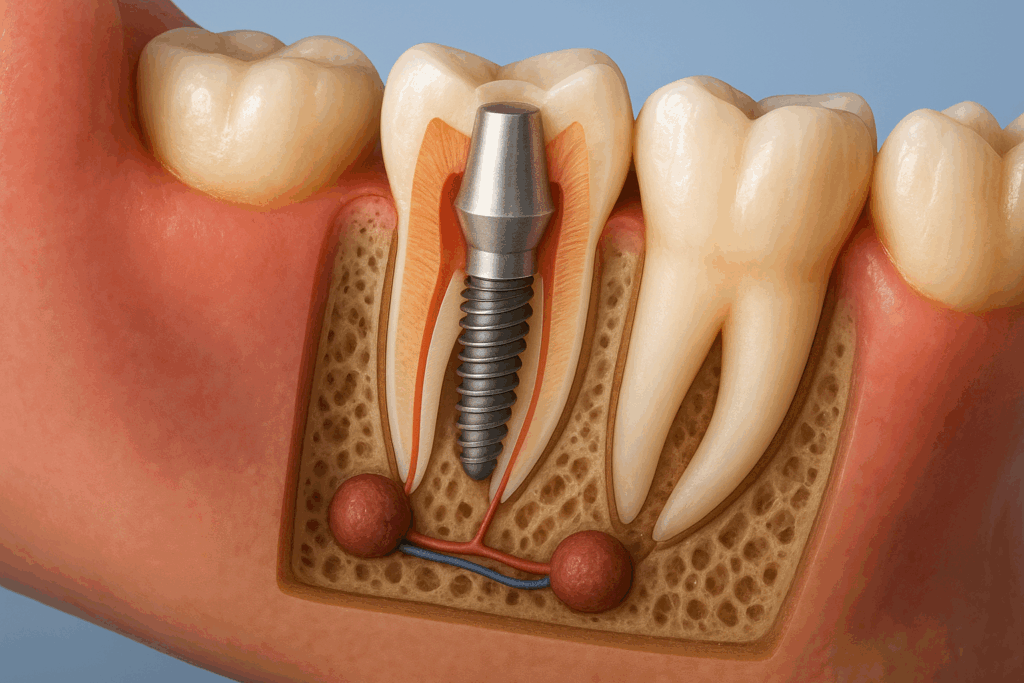

Pivotul dentar este un dispozitiv protetic care susține și reconstruiește un dinte afectat profund, în special după o intervenție la rădăcina dintelui. Practic, este un suport introdus în rădăcina dintelui, care va ține stabilă o coroană dentară.

Pivotul dentar NU este același lucru cu o înlocuire completă a dintelui cu implant – el păstrează rădăcina naturală.

Un pivot dentar are două componente principale:

- Partea radiculară – se inserează în canalul rădăcinii și oferă stabilitate.

- Partea coronară – susține coroana dentară și oferă forma necesară reconstrucției.